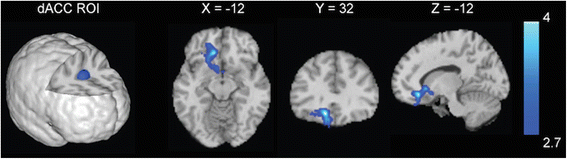

Analyses examining menstrual cycle phase differences in resting-state connectivity in cigarette-dependent women revealed no significant differences in rsFC of the mOFC between FPs and LPs. For the dACC, FPs showed decreased rsFC between the dACC and a large cluster spanning the left subgenual anterior cingulate cortex (sgACC), mOFC, and ventral striatum compared with LPs (Fig. 1). FPs also exhibited increased connectivity strength between the dACC and a cluster in the supplementary motor area/precentral gyrus compared with LPs.

Menstrual cycle phase differences in resting-state functional connectivity (rsFC) strength. Compared with cigarette-dependent women in the luteal phase of their menstrual cycle (LPs), cigarette-dependent women in the follicular phase of their menstrual cycle (FPs) showed decreased rsFC strength between the dorsal anterior cingulate cortex (dACC) seed region and a large cluster spanning the mOFC, subgenual anterior cingulate cortex, and the striatum. Images are displayed neurologically (left is left)